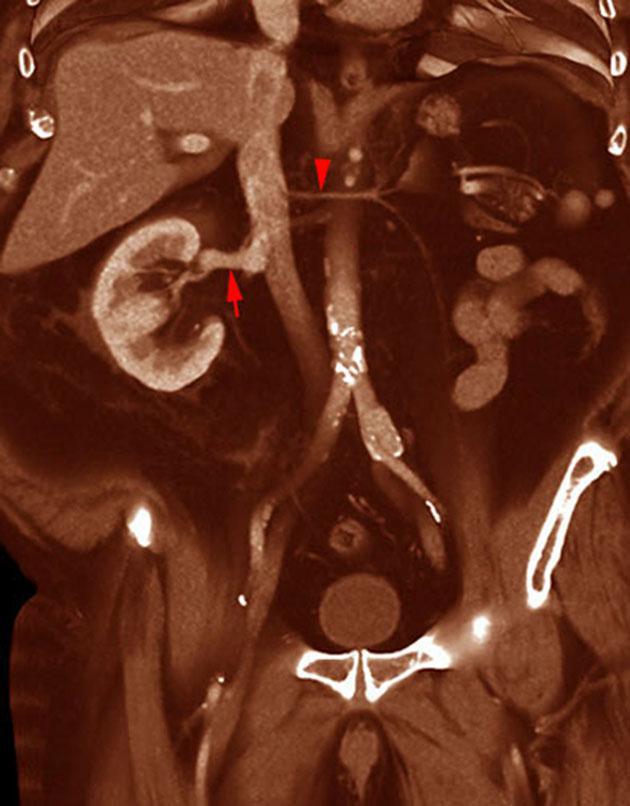

Riñón único pélvico